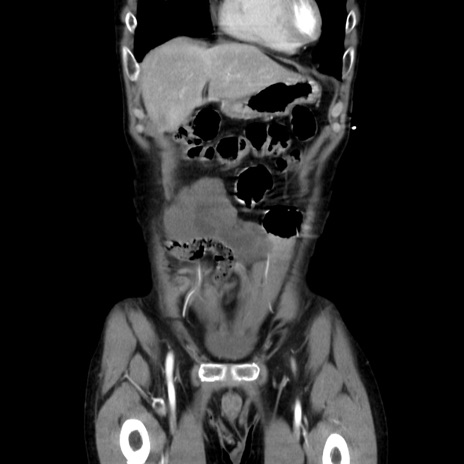

症例37(冠状断像)

【症例】40歳代 男性

【主訴】腹痛

【現病歴】4時間ほど前に電車に乗車中に臍部上より腹痛出現。徐々に増悪し起立困難となり、救急外来受診。生ものは数日食べていない。今朝お雑煮を食べた。

【身体所見】BT 36.8℃、BP 117/84mmHg、HR 91/min、SpO2 97%、苦悶様、腹部:臍上部広範囲圧痛あり、反跳痛±

【データ】WBC 8100、CRP 0.03